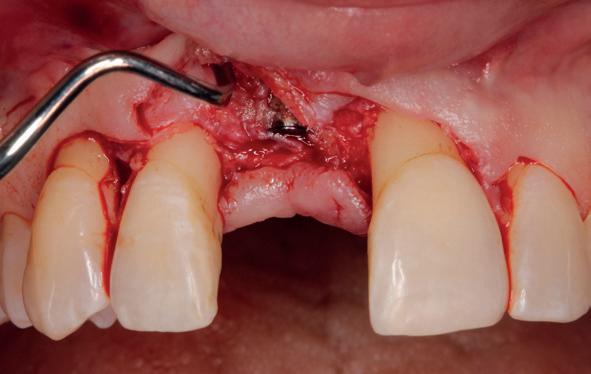

Implantologische behandelingen in het esthetische front vragen meer dan technische vaardigheid alleen. Ze vragen om overzicht, timing, vertrouwen en een team dat als vanzelf samenwerkt onder druk. Juist bij complexe casussen, waarin angst, infectie en hoge esthetische verwachtingen samenkomen, wordt zichtbaar hoe bepalend de rol van de tandartsassistent is.

Deze casus beschrijft een uitgebreide immediate implantaatbehandeling bij een patiënt die door meerdere collega’s werd geweigerd. Niet omdat de mogelijkheden ontbraken, maar omdat de complexiteit vroeg om een perfect afgestemde samenwerking. Het verhaal laat zien hoe de assistent in zo’n traject veel meer is dan een uitvoerende kracht of “mal”, maar een dynamische surgical guide die het proces mede stuurt, bewaakt en mogelijk maakt.De patiënt: wanneer alles samenkomt

Ze kwam binnen op een dinsdagochtend, iets voor achten. Een vrouw van begin zeventig, met een zachte stem en ogen die meer vertelden dan haar woorden. Ze vertelde dat ze een eigen B&B had en dat ze zich nauwelijks kon voorstellen gasten te ontvangen zonder tanden. Op dit moment kon ze echter nauwelijks lachen. “Het doet pijn… en het ruikt soms ook niet goed,” zei ze bijna verontschuldigend. Haar oude bovenbrug, die ze al meer dan twintig jaar droeg, was langzaam maar zeker ingestort. Er was sprake van cariës onder meerdere pijlers, pusafvloed,

chronische ontsteking en een brug die mobiel was en elke beet pijnlijk maakte. Ze had inmiddels meerdere tandartsen bezocht. Drie hadden haar geweigerd. Te complex. Te veel wensen. Te onvoorspelbaar.

De kern van haar vraag was eenvoudig en tegelijkertijd uitdagend: Is het mogelijk om mijn huidige brug te dupliceren en een nieuwe brug te vervaardigen met minder complicaties?

De basis van een complexe beslissing

Mijn behandelplan begint altijd met een uitgebreid klinisch onderzoek. Dat omvat een medische anamnese, intra- en extra-orale camerafoto’s en uitgebreid verwachtingsmanagement. In deze fase is mijn assistent vooral bezig met het zorgvuldig vastleggen van alle gegevens. Juist dat nauwkeurig documenteren zorgt voor rust in de behandelkamer. Minstens zo belangrijk is het luisteren naar de patiënt. Niet alleen naar de klachten, maar naar het

levensverhaal en de mens achter de brug. Begrijpen wat deze behandeling voor iemand betekent, is cruciaal voor het uiteindelijke succes.

Na het klinische onderzoek volgde het röntgenologisch traject. De CBCT liet precies zien wat we al vreesden: een front waarin het bot onregelmatig was, duidelijke radiolucenties rond de pijlers en een infectiegebied dat zich onder vrijwel de gehele brug had verspreid. Tegelijkertijd was er ook potentie. Net voldoende botstructuur om immediate implantaatplaatsing te overwegen, mits alles perfect gepland zou worden.